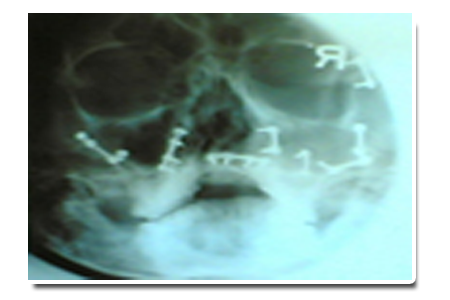

X-ray view of plating surgery done in all facial bones as shown below: